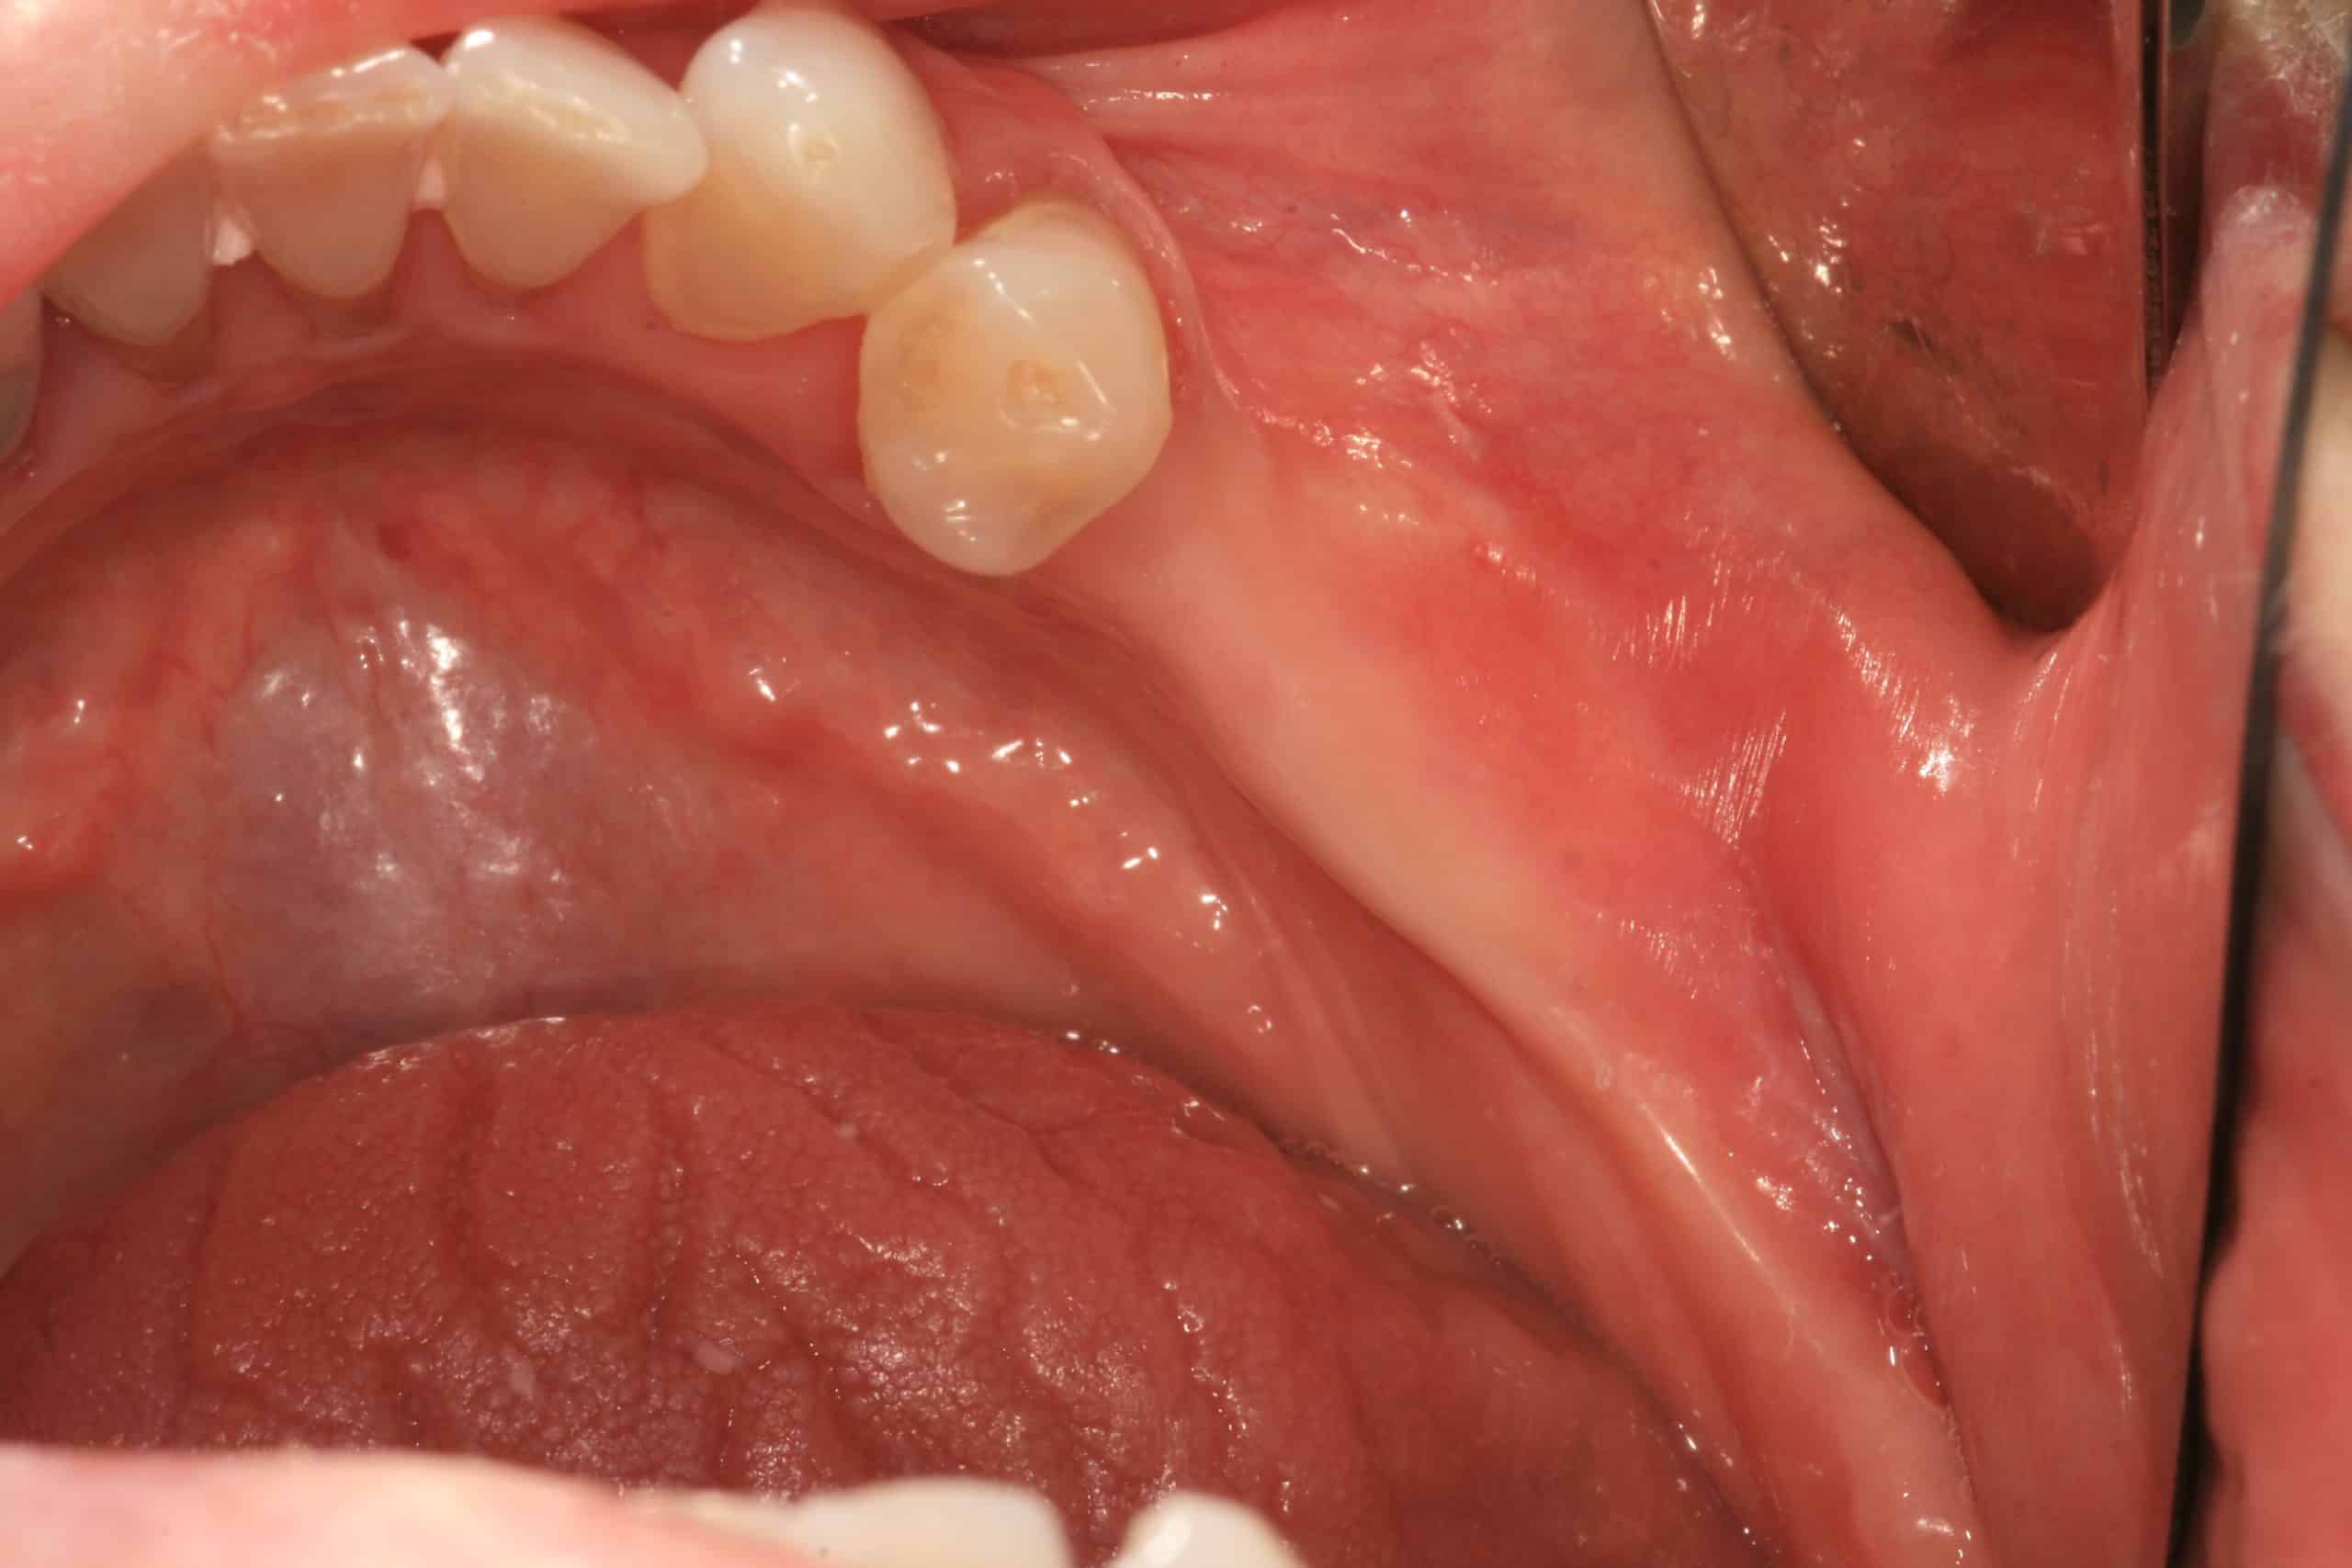

Implants Placed After Tunnel Graft Healed Advanced Dentistry & Dental Tunnel Dental Definition tunneling technique (tun) has been introduced as a minimally invasive and highly esthetic treatment option for the. the modified tunnel technique showed successful mean root coverage in the delicate anterior mandible and was able to increase the. the tunnel technique is a minimally invasive surgical approach to treat gingival recession. When applied to the right clinical. . Tunnel Dental Definition.

Steps of tunnel restoration in Tooth 15. (A) Occlusal view of 15 before Tunnel Dental Definition tunnel (tun) technique is normally performed in combination with soft tissue grafts, either autogenous connective tissue graft (ctg) or. the aims of this paper are to give a brief history of the tunnel restoration, to describe and illustrate one way of. the modified tunnel technique showed successful mean root coverage in the delicate anterior mandible and was. Tunnel Dental Definition.